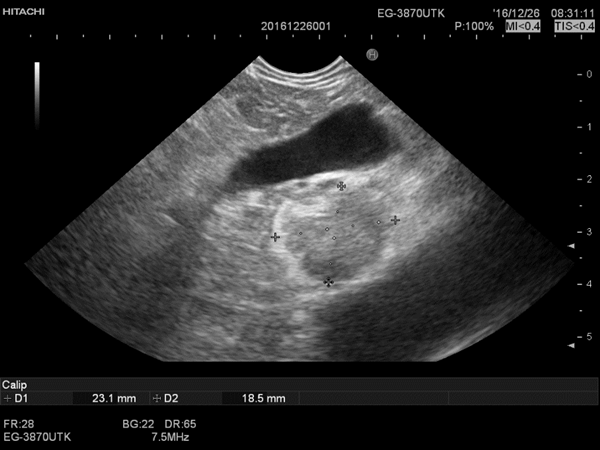

首次超声内镜检查:病变位于胰头近钩突位置,截面椭圆形血供丰富。

2016.12.22.行FNA穿刺活检与无水乙醇消融术,将穿刺针准确刺入。病变内留取样本送检,超声监控下注射无水乙醇1.6ml。

消融4日后复查超声内镜后表现为中等偏高回声病灶,血管消失